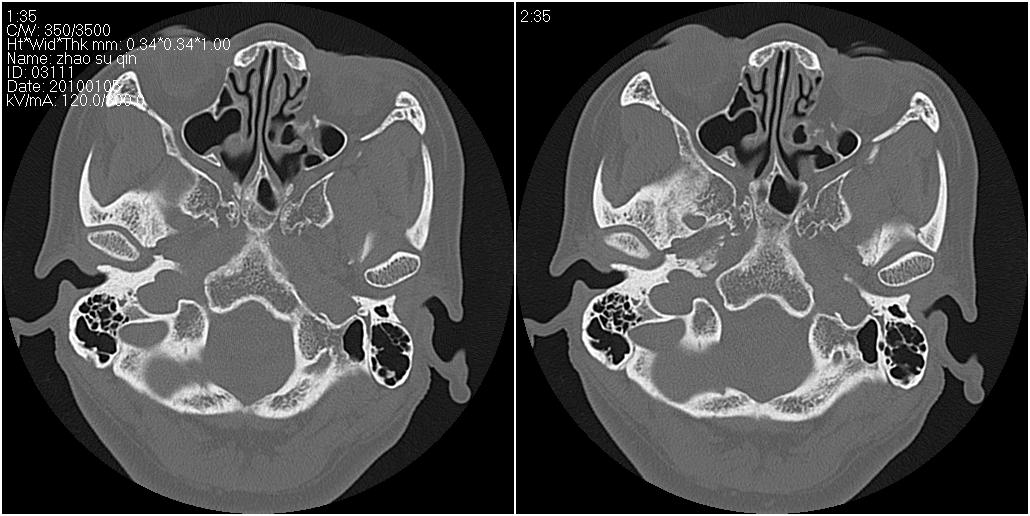

标题: CT24015:一个头部外伤患者进行鉴定,除了左侧筛板骨折,哪 [打印本页]

标题: CT24015:一个头部外伤患者进行鉴定,除了左侧筛板骨折,哪

看了几遍,其余未见明显骨折征。

左眶下裂部好像有骨折 似有小碎骨片

1)左侧筛板骨折。2)双侧筛窦炎症(或积血)。

其余未见明显骨折征。

请明示骨折部位。